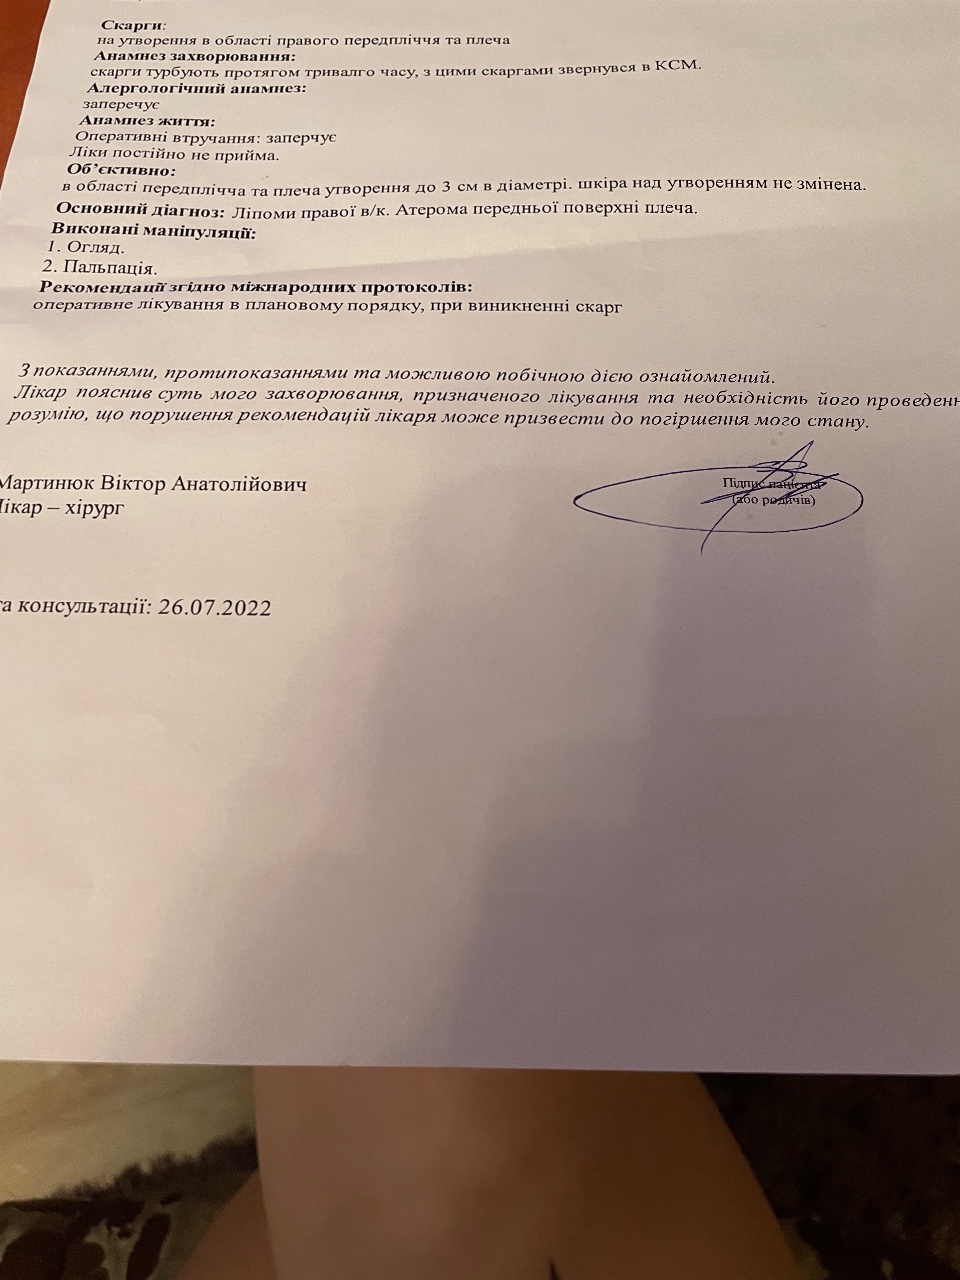

Код мкб 10 атерома головы

Код мкб 10 атерома головы 109 фото